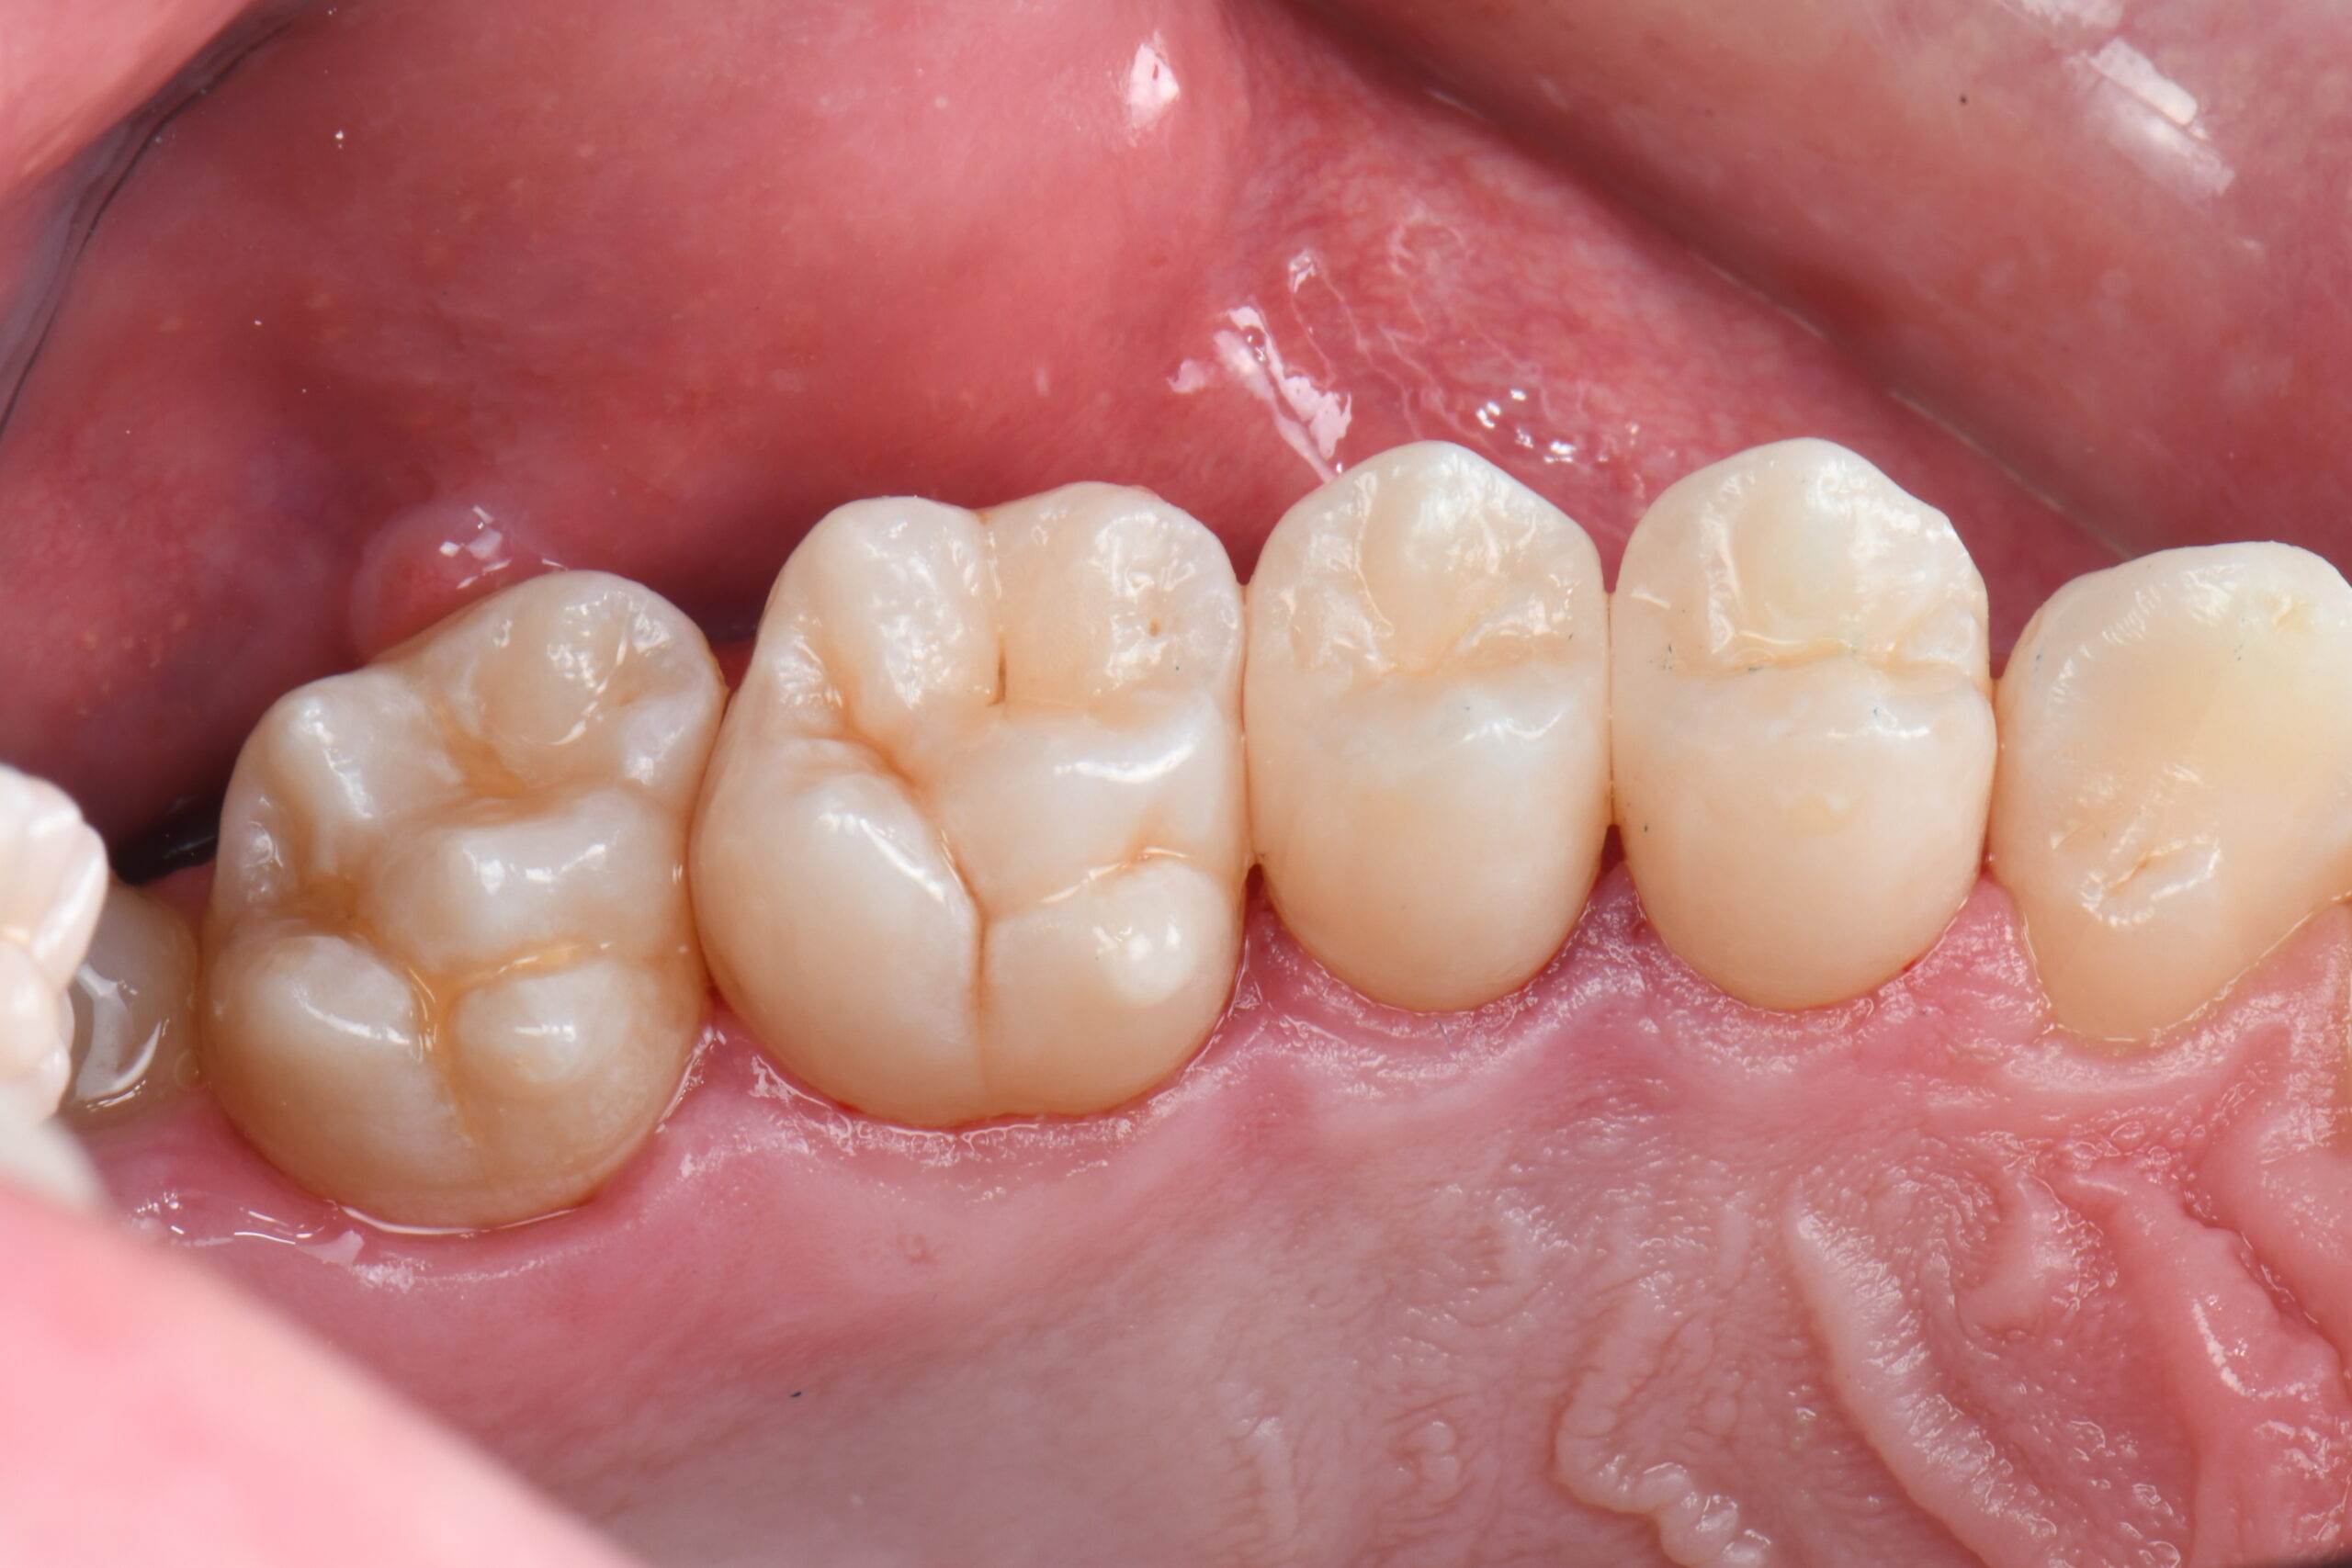

Close-up of six lower molars and premolars with visible occlusal surfaces and surrounding gum tissue

Immediate occlusal post-op photo after rubber dam removal and occlusal adjustments.